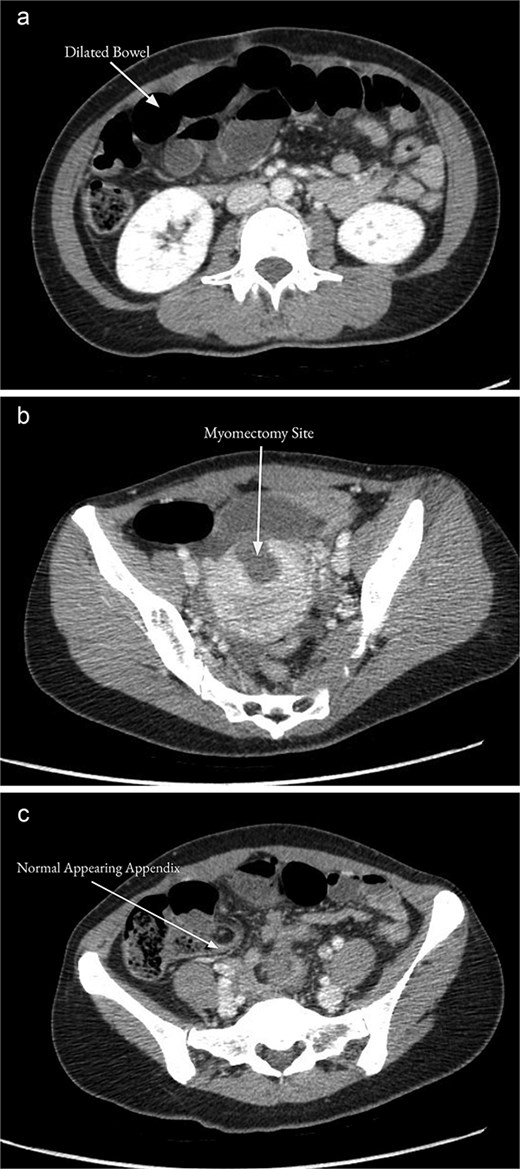

On examination, the patient was alert, oriented, and appeared uncomfortable but in no acute distress. Her abdomen was soft but distended with diffuse palpation tenderness. There was no rebound tenderness or guarding. Her supraumbilical incision was clean, dry, and intact. Laboratory workup was unremarkable, including a normal white blood cell count (WBC, 9.6 × 103/μL), hemoglobin (13.2 g/dL), and hematocrit (40.1%). Computed tomography (CT) of the abdomen and pelvis with contrast demonstrated multiple distended mid-distal small bowel loops with a transition to decompressed bowel in the right lower quadrant, consistent with a possible mid-small bowel obstruction (Fig. 1a). There was a small hemoperitoneum and focal low density along the uterine myometrium consistent with the history of myomectomy (Fig. 1b), and a normal-appearing appendix (Fig. 1c).

CT of the abdomen and pelvis with contrast on the day of admission showed multiple distended mid-distal small bowel loops indicating a possible small bowel obstruction (a). There was focal low density along the uterine myometrium consistent with the history of recent myomectomy (b). The appendix appeared normal (c).